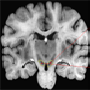

substantia nigra

MRI of

horizontal section in

human